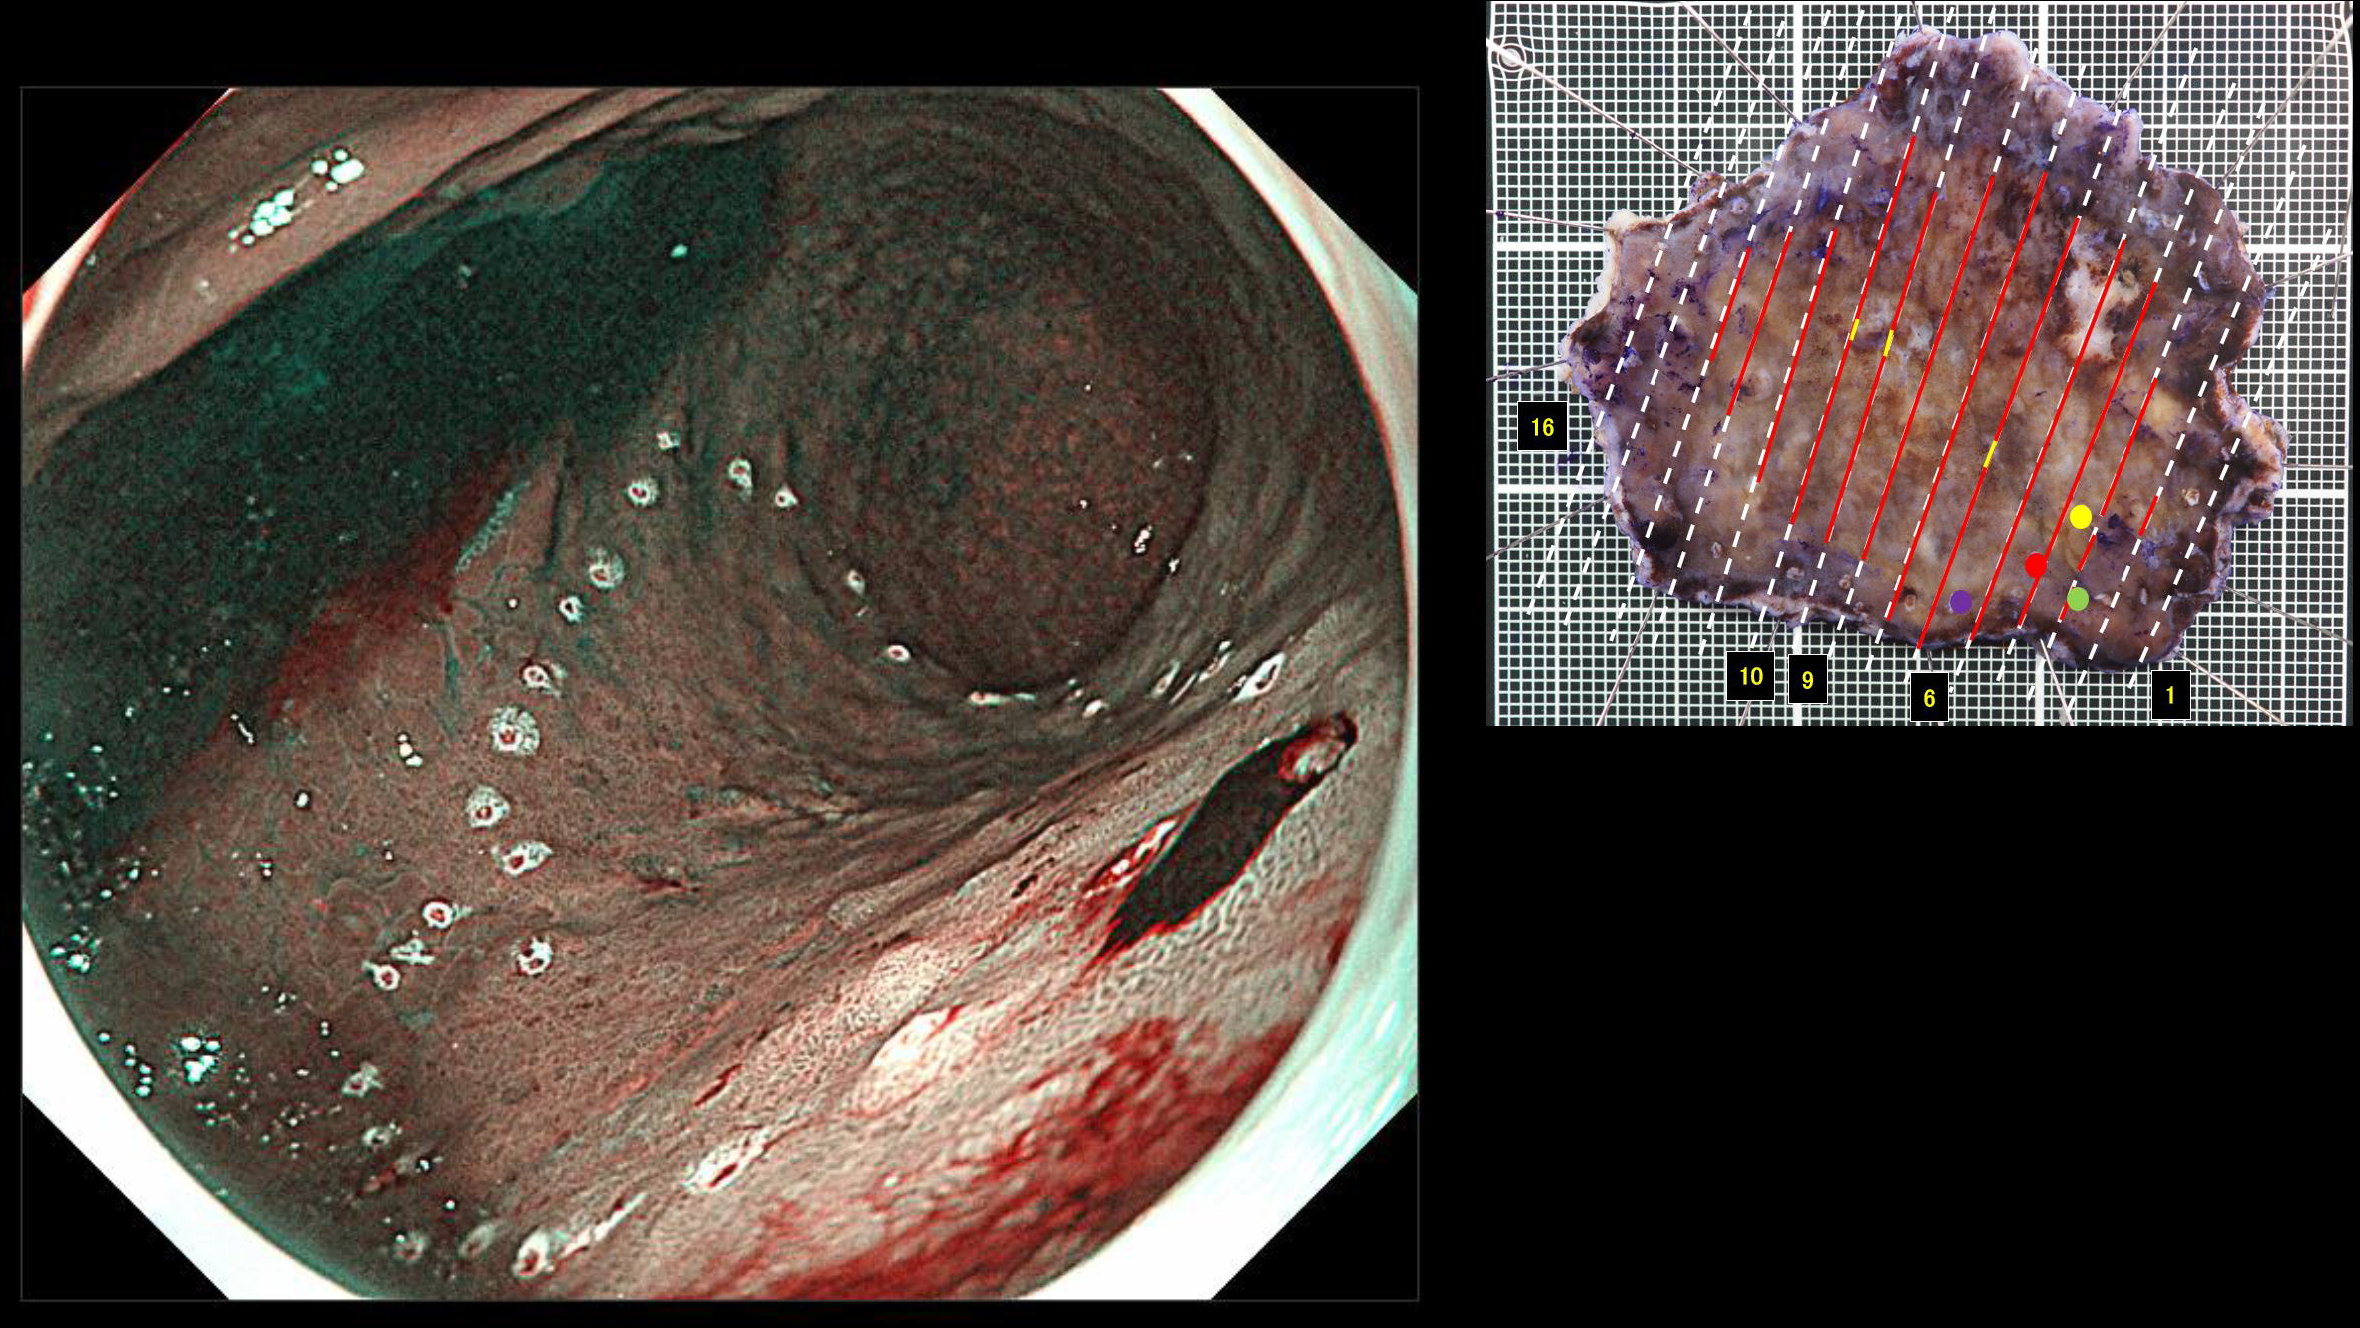

ホーム > 診療科・部門案内 > 消化器センター 消化器内科 > 消化管Mapping > 消化管Mapping~胃~ > 消化管Mapping~胃~ 2025.9.10